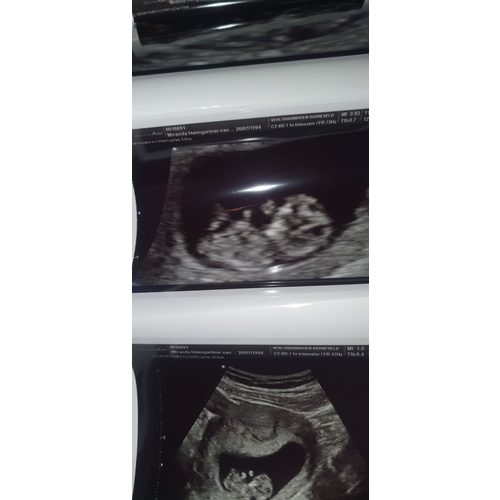

Dit was mn 12 weken echo 😅

Nu al eigenwijs ding dus ze zal wel echt van mij zijn vrees ik